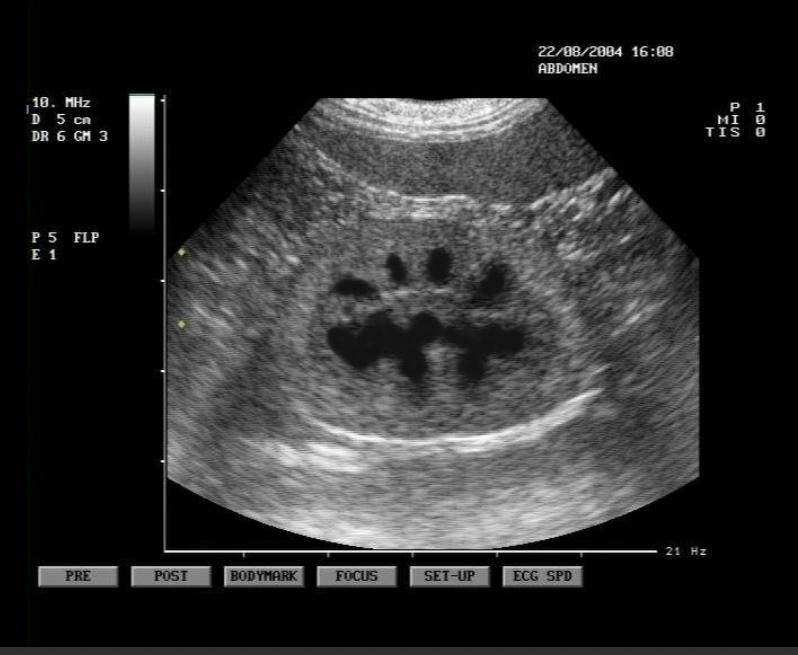

Kidneys

pelvis, cortex, and capsule are visible

adrenal glands are a dumbbell shape and are just cranial to the kidneys

Function:

- production of urine to facilitate the elimination of metabolic waste materials from the body

- helps maintain homeostasis by manipulating the composition of blood plasma